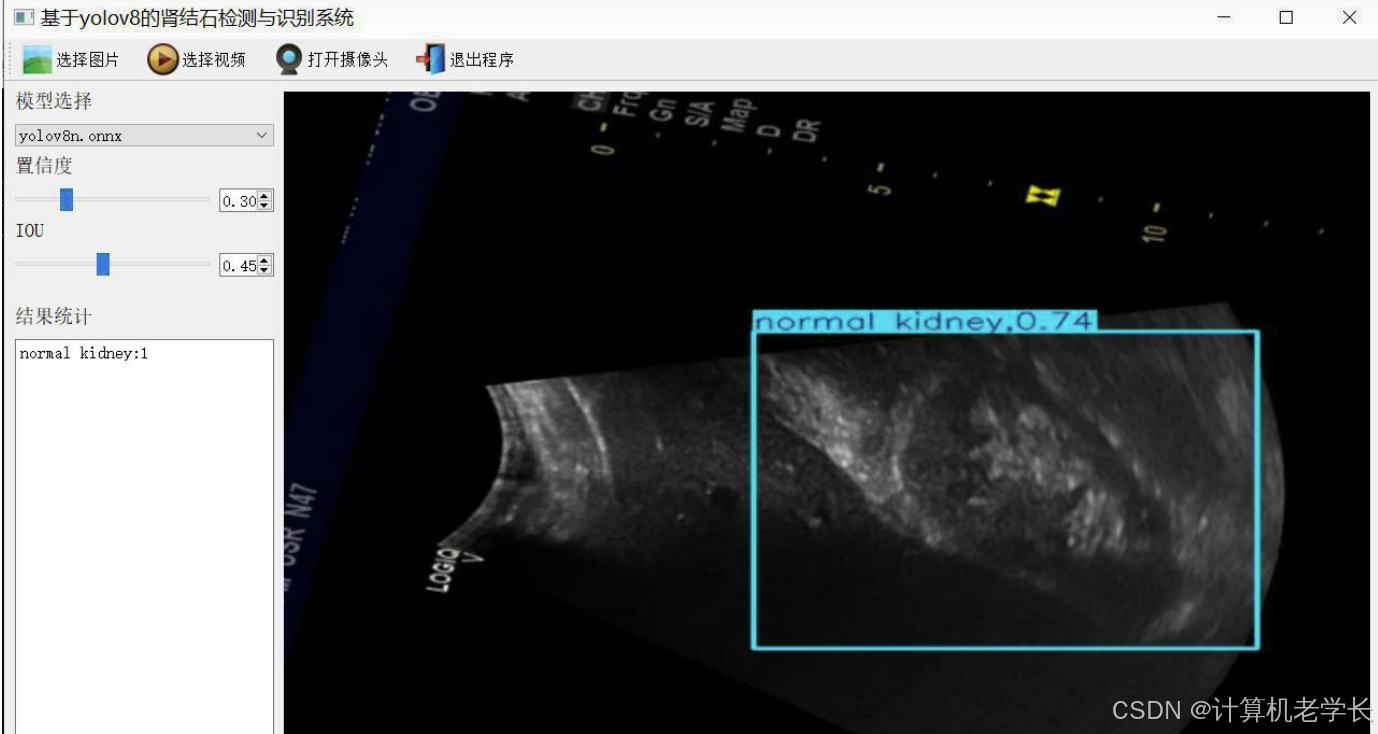

5.2 实验截图

本系统通过YOLOv8模型实现了肾结石的精准检测,实验结果表明系统在准确率和检测速度方面表现良好,能够满足实际应用需求。未来将继续优化模型性能,提升系统稳定性和扩展性。